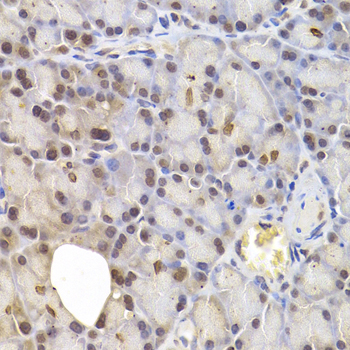

• A6246: image 2

Immunohistochemistry of paraffin-embedded rat pancreas using IRF6 antibody at dilution of 1:200 (400x lens).